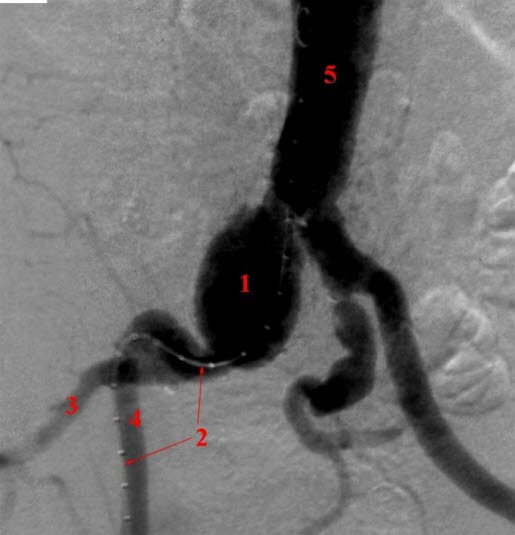

Angiografi

Aneurisme i høyre arteria iliaca communis.

- Aneurismet (utposning)

- Kateter

- A. iliaca interna

- A. iliaca externa

- Aorta